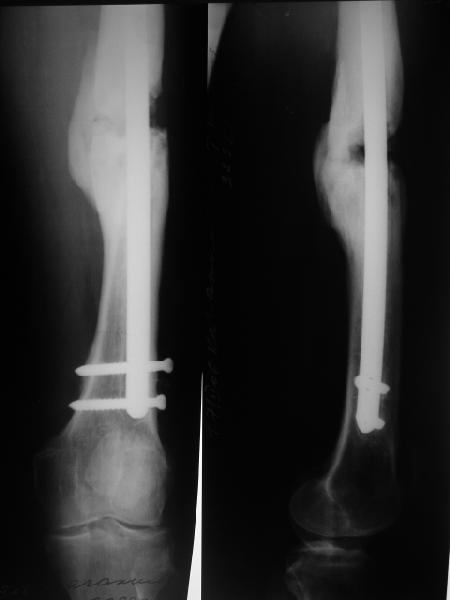

В приложении снимки бедра - с такой картинкой пациентка ходит, не хромает, работает инженером 3,5 года после операции с первых дней, хотя еще и инсулинозависимый диабет.

У нас есть все же сомнения, насколько он "тугой". Наличие хоть и нестабильной но все же фиксации пластиной, маскирующей степень подвижности; сочетание на рентгенограммах зон гиперостоза с зонами лизиса не дает четкой уверенности ни в том, что это тугой ложный сустав в классическом понимании, ни что это истинно атрофическая ситуация. А чем сейчас можно быть уверенным? Вот потому и одолевают сомнения.

> В приложении снимки бедра

Очень убедительно.

Наш пациент имеет рост 2 м и вес 120 кг, при этом он не выглядит полным. Так что не очень хочется надеяться только на гвоздь, хотелось бы и репаративные процессы обеспечить.